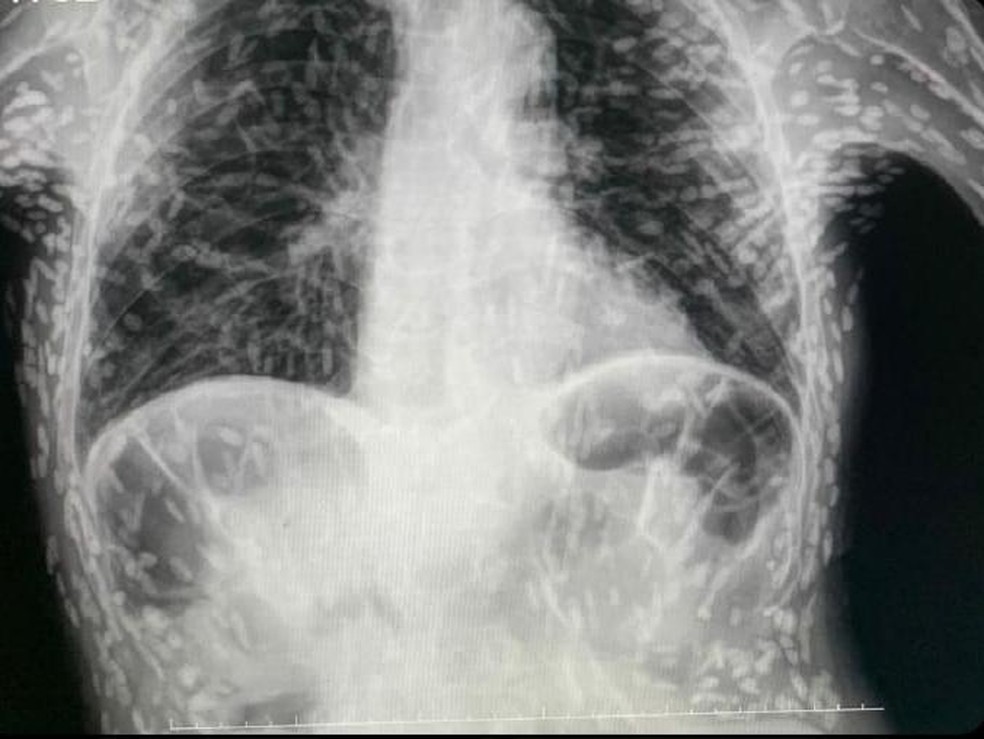

Médico usa raio-x de paciente infestado de ovos de tênia e pede atenção no preparo de carne de porco; entenda — Foto: Reprodução

Em abril do ano passado,um caso de exame semelhante viralizou também no Brasil. Um paciente não identificado teve seu exame revelado nas redes sociais pelo Hospital das Clínicas de Botucatu,em SP. O paciente apresentava tosse constante há dois meses quando o exame foi solicitado. Os ovos de tênia encontrados no tórax já estavam mortos e calcificados,ou seja,não apresentavam risco a ele.

Os ovos de tênia encontrados no tórax já estavam mortos e calcificados,já não apresentavam riscos — Foto: Reprodução/ Twitter